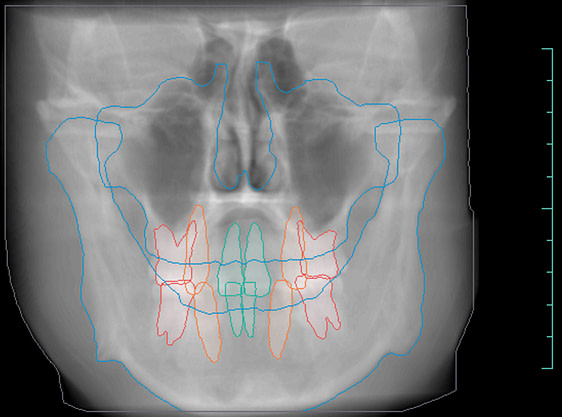

Diagnocat generates OPG and frontal and lateral cephalometric reconstructions from the CBCT data.

Tracings of the maxilla, mandible, central incisors, canines and molars. All automatically.

Cross-sectional and coronal views of teeth show torque and buccolingual relationships such as crossbite.

The orthodontic report generates OPG and front/lateral cephalograms. These are not as sharp as true OPG and cephalograms. Tracings of the maxilla, mandible, central incisors, canines, and molars are automatically produced on the generated frontal/lateral cephalogram.